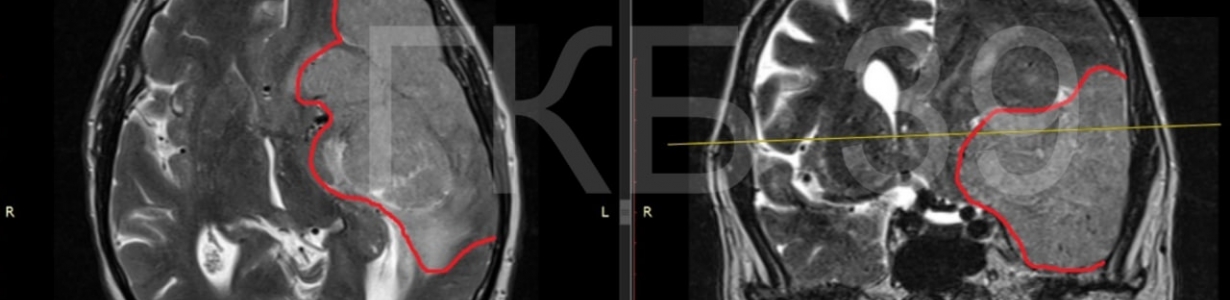

Медики увидели опасное новообразование в голове у пенсионера во время консультации. Его сразу же госпитализировали. К тому моменту 10-сантиметровая опухоль заняла практически треть полушария мозга, сдавив лобную, височную и теменную доли. Кроме того, она смещала мозг.

На удаление «гиганта» с помощью микрохирургической техники у команды нейрохирургов ушло 4,5 часа. Через десять дней мужчину отпустили домой в удовлетворительном состоянии. Как оказалось, опухоль была доброкачественной. Сейчас пенсионер уже вернулся к полноценной жизни.